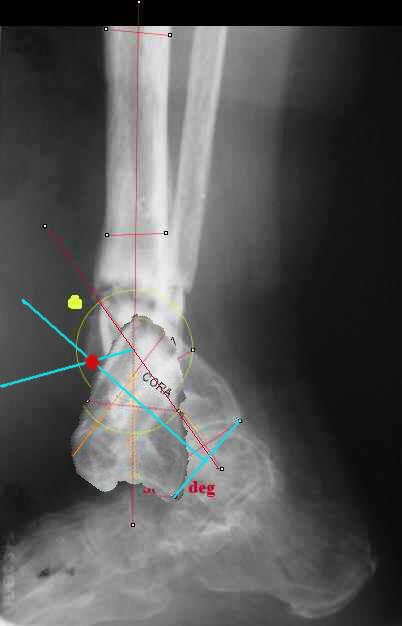

I played with your image using some orthopedic software we have been developing for digital

image analysis.

What you see marked up is the intercept of two mid-line tool centre lines, used to define the CORA. An angle tool gives the angular deformity and a circle tool is applied to show that a correction around the CORA through the old # will restore alignment without much translation.

I looked at your image. I presume your yellow marker is the hinge axis? I think this should be at the CORA.